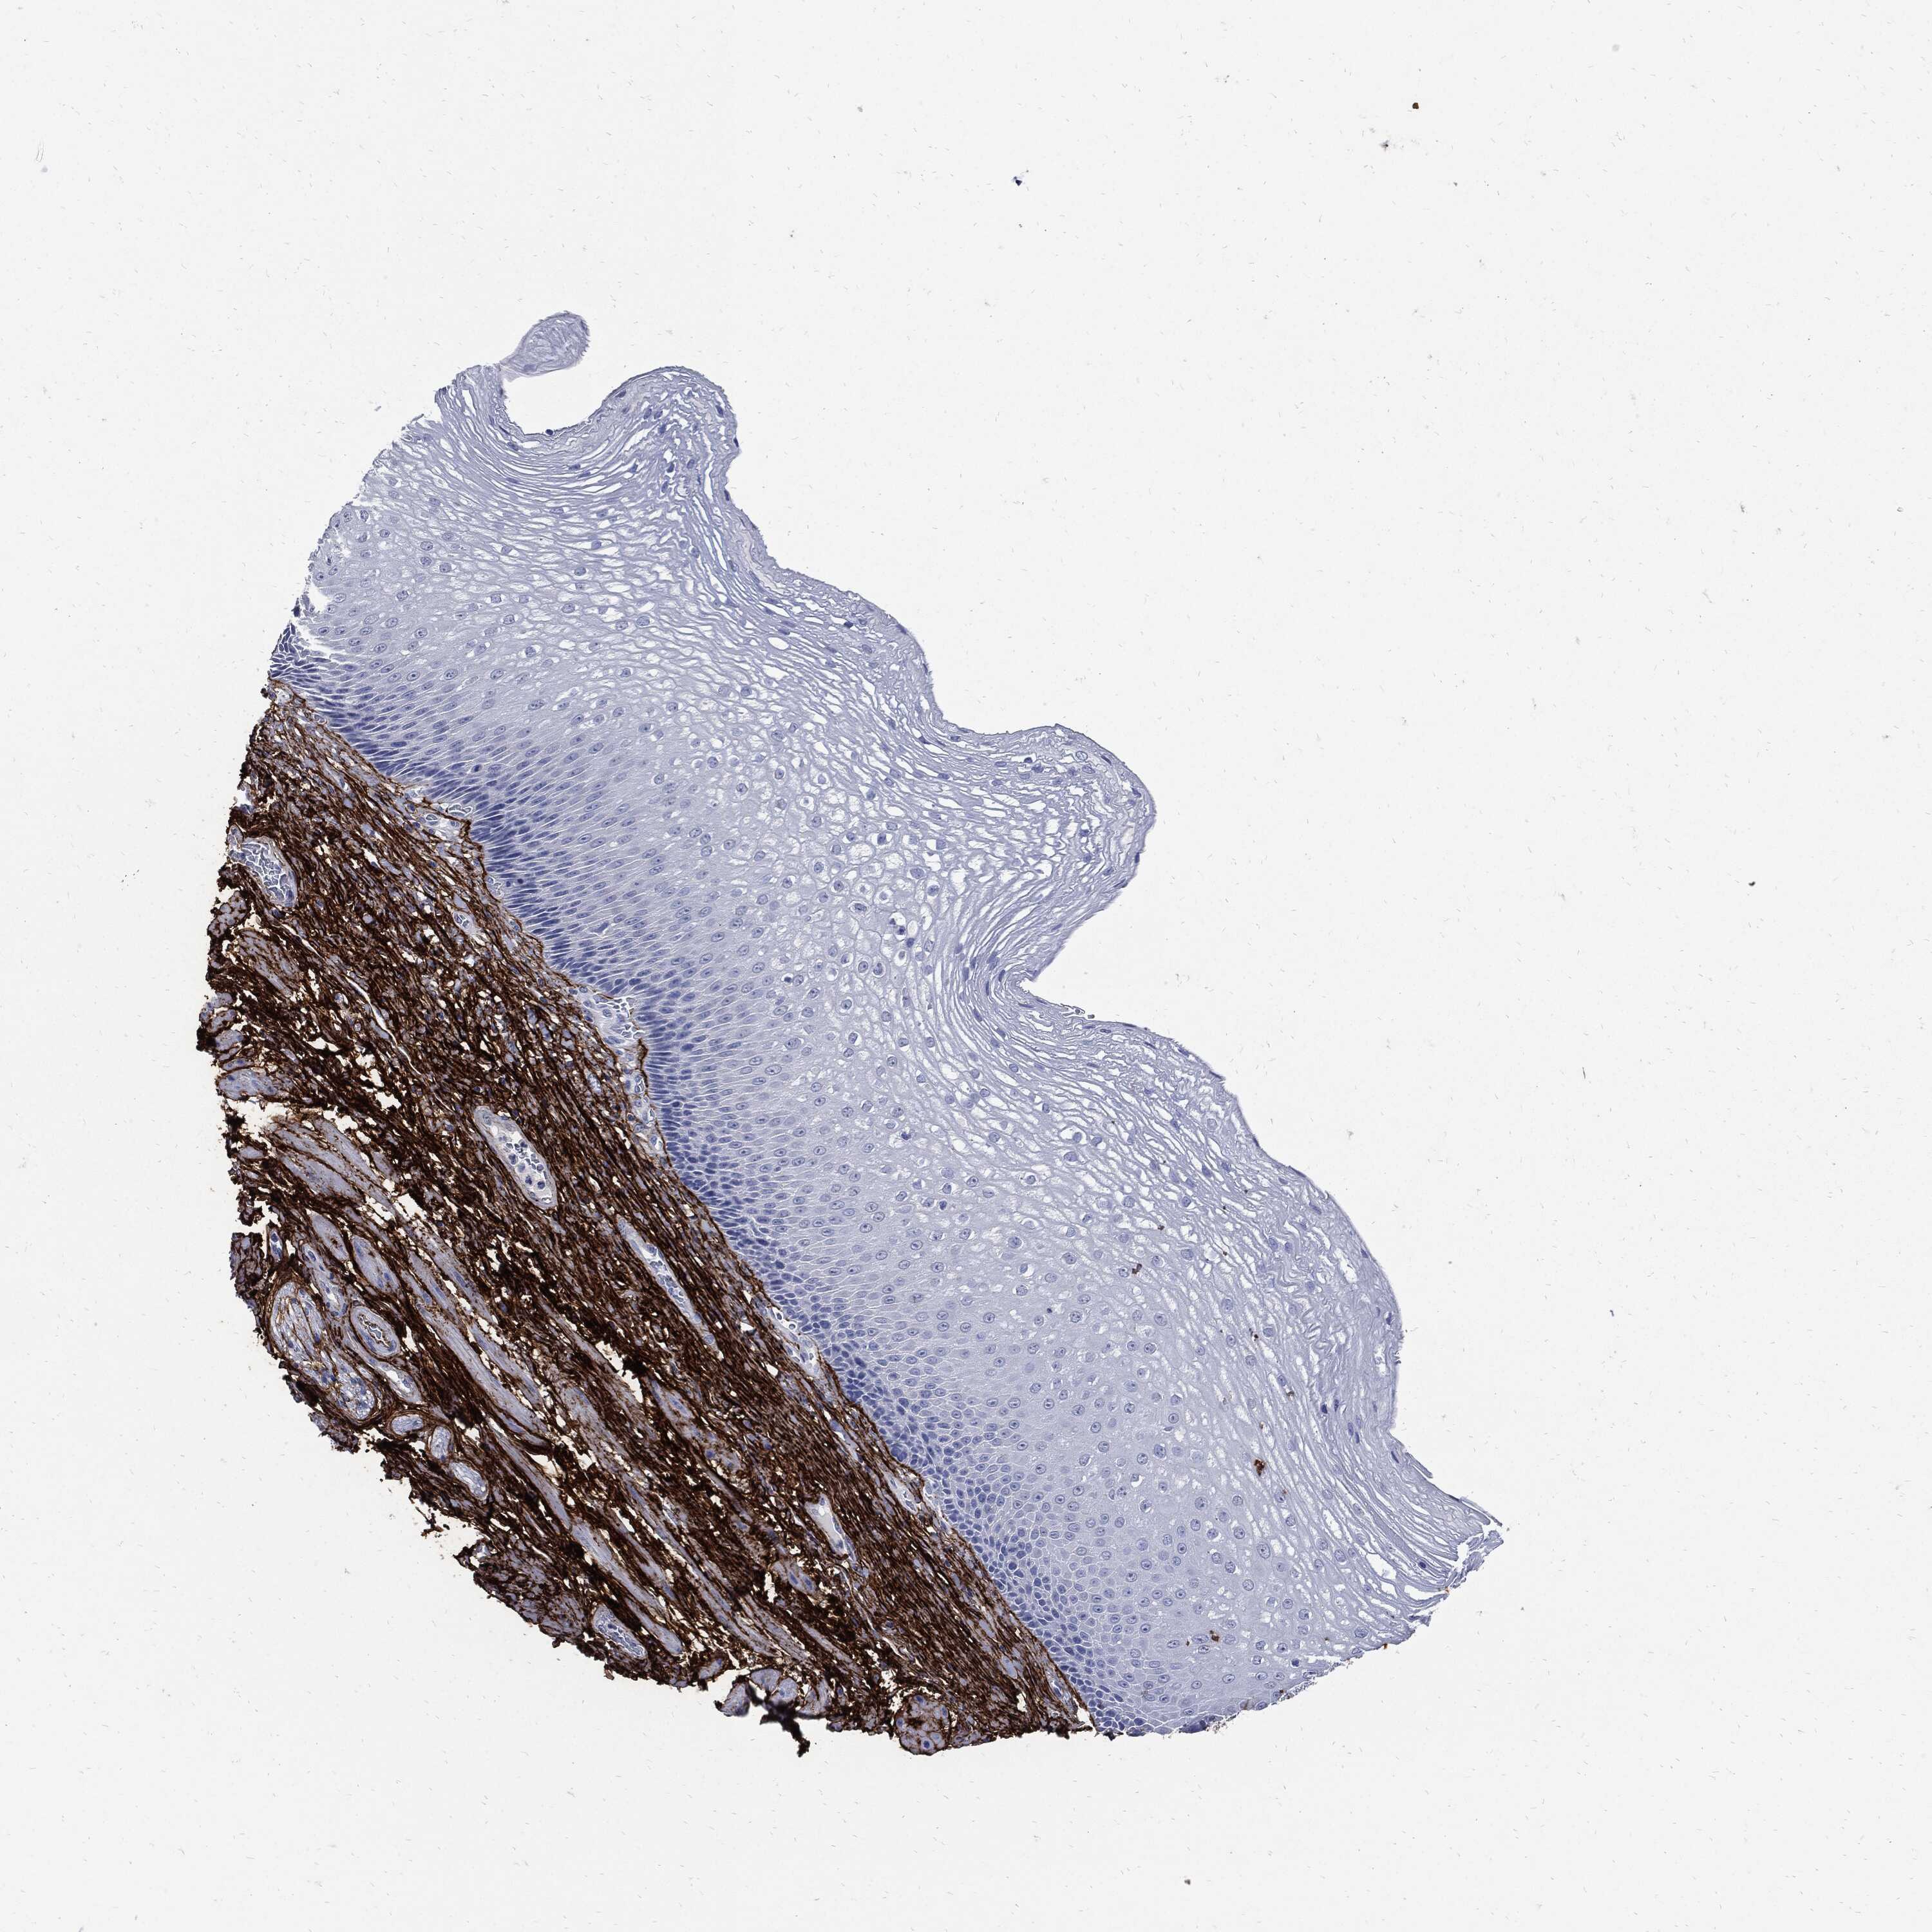

ESOPHAGUS - Antibody stainingi

Antibody staining in the annotated cell types in the current human tissue is reported as not detected, low, medium, or high, based on conventional immunohistochemistry profiling in selected tissues. This score is based on the combination of the staining intensity and fraction of stained cells.

Each image is clickable and will lead to virtual microscopy that enables deeper exploration of all samples and also displays staining intensity scores, fraction scores and subcellular localization as well as patient and tissue information for each sample.

Antibody HPA017759Antibody HPA021057Antibody CAB002670Antibody CAB058696Antibody CAB068188Antibody CAB080202

Squamous epithelial cells Not detectedNot detectedNot detectedNot detectedNot detectedNot detected